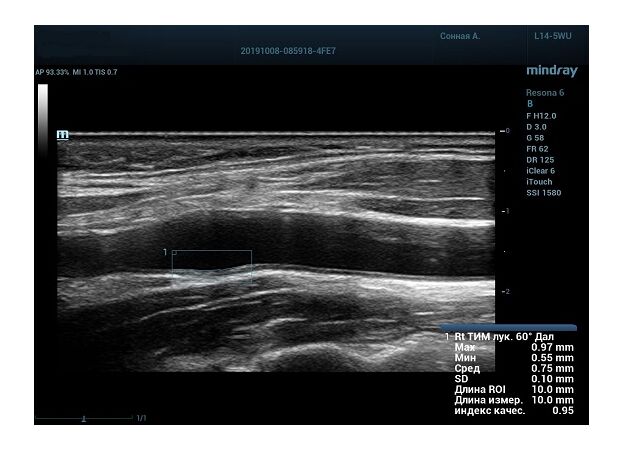

Функция в ультразвуковых аппаратах

На сегодняшний день измерение IMT происходит автоматическим путем при использовании функции AUTO-IMT. Необходимо указать прибору зону интереса, стандартной длиной (1 см), в которой происходит отслеживание кромок и выдача максимального, среднего и минимального значения. УЗИ аппараты компании Mindray среднего, экспертного и премиального класса снабжены данной функцией и позволяют контролировать не только полученные значения, но и оценить точность измерения кромки в конкретной зоне по индексу качества. Используя индекс качества, легко решить, можно ли использовать полученное значение.